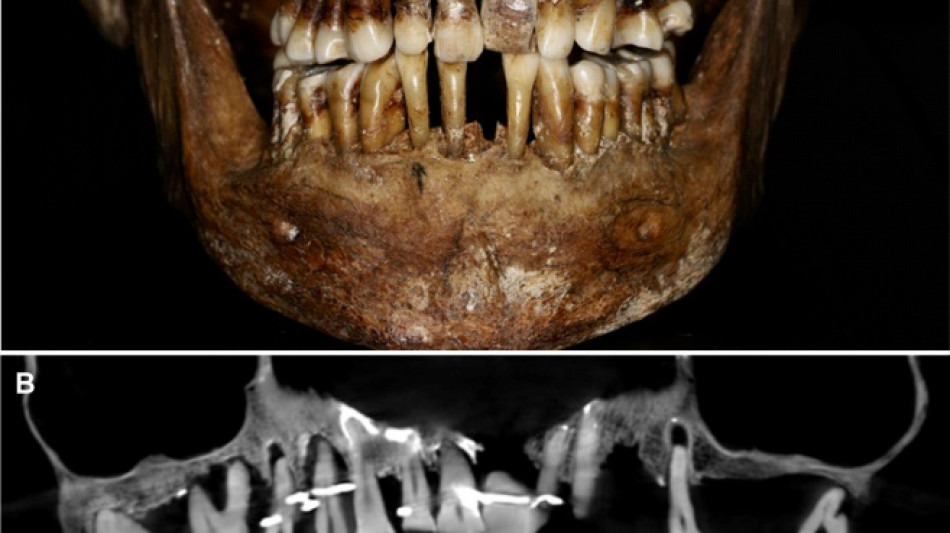

French aristocrat's golden dental secret revealed 400 years on / Photo: © INRAP/Rozenn Colleter/AFP/File

Embalmed in a lead coffin, her skeleton -- and teeth -- were remarkably well preserved.

Thirty-five years later, a team of archaeologists and dentists have identified that d'Alegre suffered from periodontal disease that was loosening her teeth, according to a study published in the Journal of Archaeological Science: Reports this week.

A "Cone Beam" scan, which uses X-rays to build three-dimensional images, showed that gold wire had been used to hold together and tighten several of her teeth.

She also had an artificial tooth made of ivory from an elephant -- not hippopotamus, which was popular at the time.